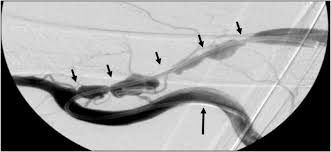

Central Venous Stenosis (CVS)

CVS refers to venous obstruction within the central veins, such as the subclavian, brachiocephalic, or superior vena cava, that impairs drainage from the head and upper extremities The etiology often includes intimal injury from prior intravascular devices, external compression, or thrombosis. Pathophysiologic changes such as intimal hyperplasia, thrombus formation, or extrinsic compression contribute to luminal narrowing and obstructed flow.

The incidence of CVS ranges widely, from 3% to 60%, depending on the population studied and the presence of risk factors such as prior CVCs. (MacRae et al. 2005) (Lumsden 1997) It is more frequently symptomatic when associated with grafts and upper arm access compared to fistulas and forearm access. (Trerotola et al. 2015) Symptoms may include extremity or facial swelling, dilated collateral veins, and inadequate dialysis delivery. A venogramremains the diagnostic gold standard for confirming stenosis and identifying its etiology. For further information on physical exam findings and surveillance strategies, please refer to the Surveillance section.

Endovascular Reinterventions

Endovascular interventions are the cornerstone of minimally invasive treatments for HD access complications, particularly for stenosis and thrombosis. Angioplasty, the primary modality, involves the inflation of an intravascular balloon within a stenotic segment to restore luminal patency. Procedural success is defined as achieving less than 30% residual stenosis after the procedure when compared to adjacent normal veins on imaging. (“Clinical Practice Guidelines for Vascular Access” 2006) Complications such as venous spasm or vein rupture occur in <1% of patients, though they are typically managed effectively with interventions like balloon tamponade or the placement of covered stents. (Beathard, Urbanes, and Litchfield 2017) Percutaneous thrombectomy and catheter-directed thrombolysis are valuable adjuncts to angioplasty as they can promptly address complications without requiring surgical revision, thus maintaining continuity of dialysis treatment. Stent placement is reserved for cases of reintervention failure due to the risk for complications. Indications include acute angioplasty failure, rapid recurrence, and vein rupture following angioplasty. (Dariushnia et al. 2016) For cases of CVS, initial treatment often involves balloon venoplasty, with stenting reserved for similar situations as patency rates following venous stenting are relatively low. (Dariushnia et al. 2016)